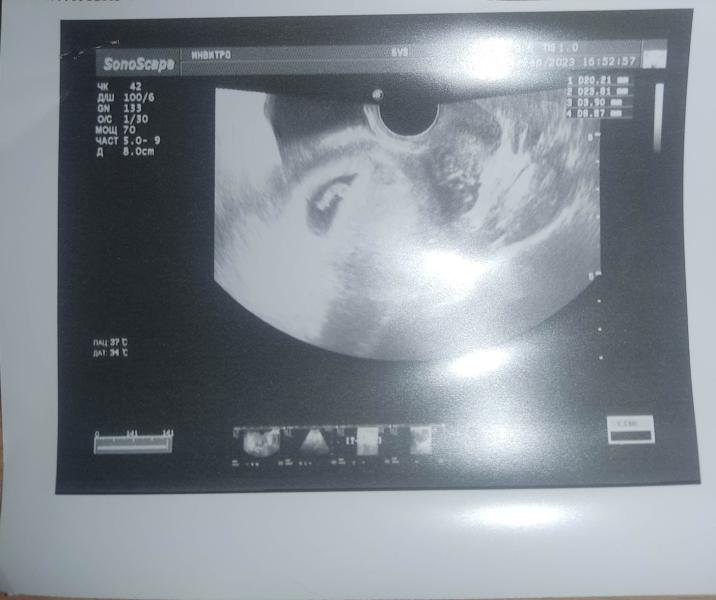

Первое УЗИ 7-8 недель: смотрим фото, в приложении показывает 6 недель 2 дня - как это понимать?

Наше первое фото🥰 по узи 7-8 недель, в приложении 6 недель 2 дня